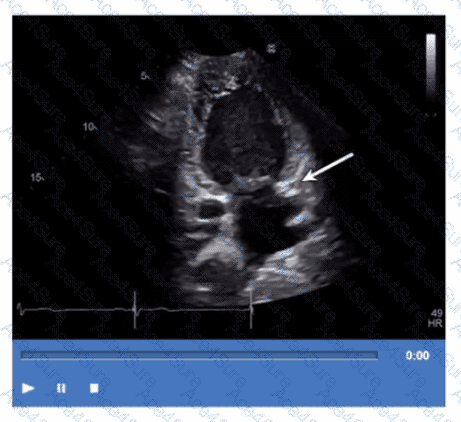

Which structure is the arrow pointing to in this video?

The arrow points to the coronary sinus, which is a venous structure located posteriorly in the atrioventricular groove, emptying into the right atrium. It appears as a circular anechoic structure near the left atrium in echocardiographic images.

Left lower pulmonary vein enters the left atrium more superiorly. Descending aorta is posterior to the heart but not in this location. Left atrial appendage is an anterior finger-like projection of the left atrium, separate from the coronary sinus.